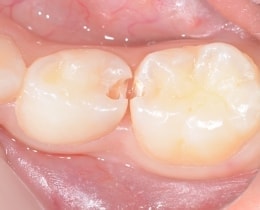

①治療前

お口の中をみただけでは、歯と歯の間に虫歯があるかどうか、わかりにくいです。